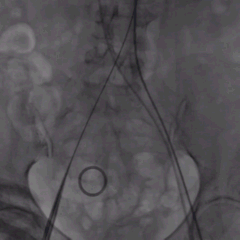

术中影像:

双侧侧髂血管造影血管纤细

LCA保护下18mm球囊预扩,扩张充分,瓣叶向LCA开口偏移;输送器过弓顺利。

瓣环下精准定位稳定释放,瓣膜工作位造影考虑瓣叶推挤LCA阻挡临界状态,释放“烟囱支架”。

瓣膜稳定脱钩,20mm球囊后扩,“烟囱支架”Kissing,后扩后支架形态改善。

左髂动脉“翻山“,造影+覆膜支架预备伴随保护下顺利退鞘,造影观察无血管损伤,手术顺利结束。